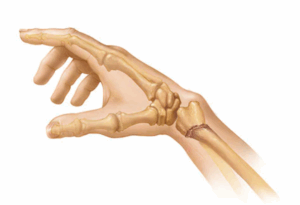

Thumb arthritis

Thumb arthritis is common with aging. The condition happens when cartilage wears away from the ends of the bones that form the joint at the base of the thumb. Cartilage is the strong tissue that connects and protects joints and bone. This joint at the base of the thumb also is called the carpometacarpal joint and the CMC joint.